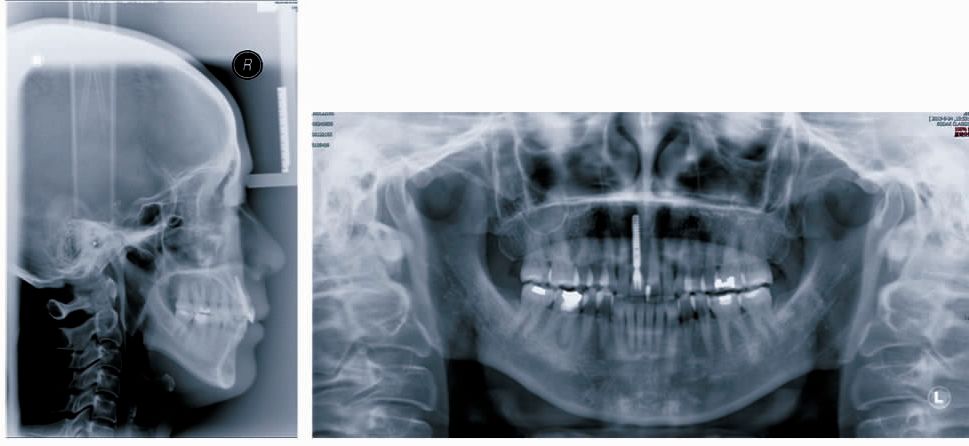

6.种植修复右上中切牙(图4)。

图4 病例种植修复后X线片及(牙合)像

矫治结果

联合治疗结束后患者面型没有改变,双侧尖牙及磨牙为中性关系。下牙列排齐并压低,前牙覆(牙合)覆盖正常。双侧颞下颌关节未发现弹响及压痛。曲面断层片未见明显的下前牙牙根吸收。头影测量显示下前牙舌向移动并压低,下颌平面角没有明显的改变(图5)。